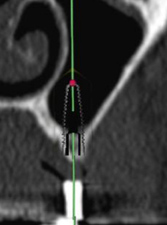

術前CT 1

第二小臼歯部

インプラントをシミュレーション

術前CT 2

第一大臼歯部